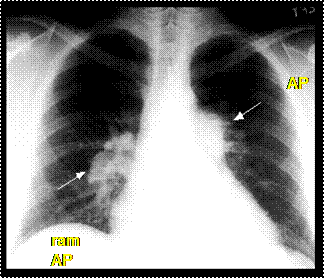

Rx cord-pulmon: circulatie pulmonara 'incarcata' cu ramurile AP dilatate in hiluri si extremitati 'retezate' avind periferie mult mai clara decat normal, bombare a conului arterei pulmonare, semne de hipertrofie VD

Imagine radiologica de HTP primara

Imagine radiologica de HTPS (DVPA) Imagine radiologica de HTPS (stenoza mitrala)

HTP secundara incipienta (DSA) HTPS severa (DSA Eisenmengerizat)